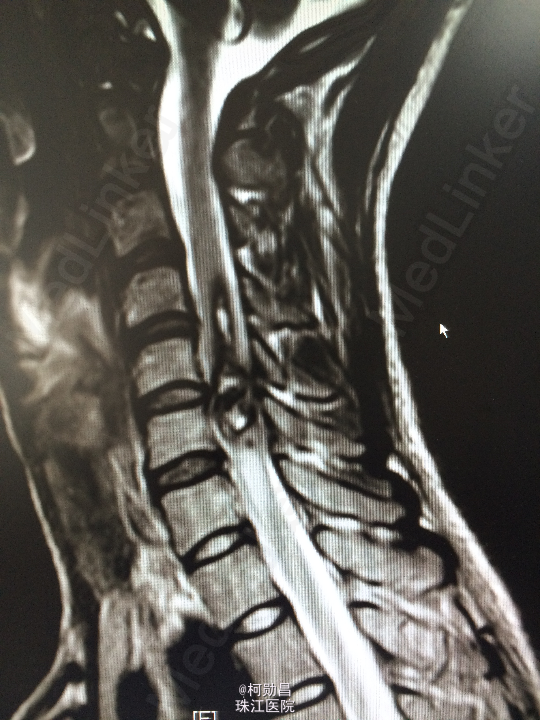

主诉:颈部疼痛伴右手麻木疼痛2月余 病史:患者缘于去年11月份无明显诱因出现右侧上肢乏力,右手小指及无名指疼痛麻木感,无头痛头晕,无间歇性跛行等,在当地医院行MR提示:颈椎椎管内占位性病变,予对症治疗后效果不佳。期间上述症状加重,遂至我院进一步诊治。

查体:颈椎下端棘突间轻压痛,颈椎活动受限,双臂丛牵拉试验阳性,压头试验阳性。四肢肌力5级,感觉:右侧前臂尺侧小指及无名指痛、触觉稍减退,余肢体及鞍区疼痛觉正常。反射:右侧肱二头肌腱反射亢进,左侧肱二头肌腱反射稍亢进,左侧肱三头肌腱反射活跃,双侧挠骨膜腱反射康静,双侧膝腱反射正常。余反射正常。病理征:右侧Hoffman征弱阳性,左侧Hoffman征正常,余征均正常。 辅助检查:颈4-6椎体水平髓内出血信号,海绵状血管瘤伴出血?

诊断:C5/6脊髓内海绵状血管瘤并出血。 处理:予手术切除治疗

海绵状血管瘤是血管先天发育畸形,由衬有内皮细胞的无数血窦组成,血窦大小、形态不一,形似海绵结构而得名。属于良性肿瘤,可予手术切除或介入栓塞治疗。本例中予手术切除,采用后入路方式,切除过程中注意保护脊髓的结构,尽量减少损伤,